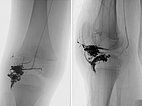

Digital subtraction angiography (DSA) of the knee (left AP projection, left lateral projection) shows an AVM with a rather spherical, aneurysmal nidus as well as another nidus intraosseously in the lateral tibial plateau. This very spherical, aneurysmal nidus together with the painful, progressive mass is suggestive of a PTEN hamartoma.

After successful embolization of the two AVM nidus parts, the radiographic overview images (left AP, right lateral projection) shows a complete cast specimen of the two portions caused by the embolic agent, the so-called cast. This consists of ethylene-vinyl alcohol copolymer, which contains radiopaque tantalum.